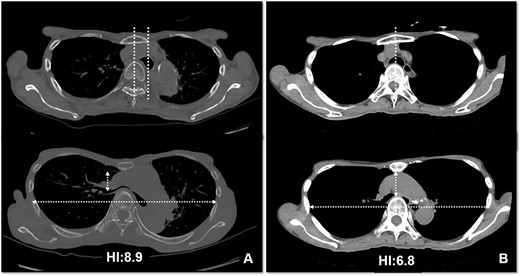

The patient was a 74-year-old woman with a history of childhood PE. Fourteen years ago, a total glossolaryngectomy was performed at another hospital for oropharyngeal cancer, and a permanent tracheal stoma was created. Approximately 2 years later, the patient gradually experienced difficulty in breathing. Chest computed tomography (CT) revealed severe PE and right main bronchial stenosis. Subsequently, the patient was referred to our department. A preoperative spirometry test showed a vital capacity of 1.14 L (45% of the predicted value). As part of the imaging test, a chest CT indicated a leftward deviation of the trachea. Symmetrical depression with a Haller Index (HI) of 8.9 and stenosis of the right main bronchus were observed at the same site (Fig. 1). The chest CT taken over 8 years indicated that the leftward deviation of the trachea had progressed and the thoracic depression had worsened (Fig. 2). Intraluminal observation using a bronchoscopy revealed severe stenosis of the right main bronchus, making peripheral observation challenging (Fig. 4A).

CT scans are used to monitor changes over time. In (A), chest CT findings of severe PE with stenosis of the right main bronchus. The trachea, which was centrally located on CT scan 8 years ago (2B), has shifted to the left now (2A). Additionally, the CT-HI worsened over his 8 years, increasing from 6.8 to 8.9.